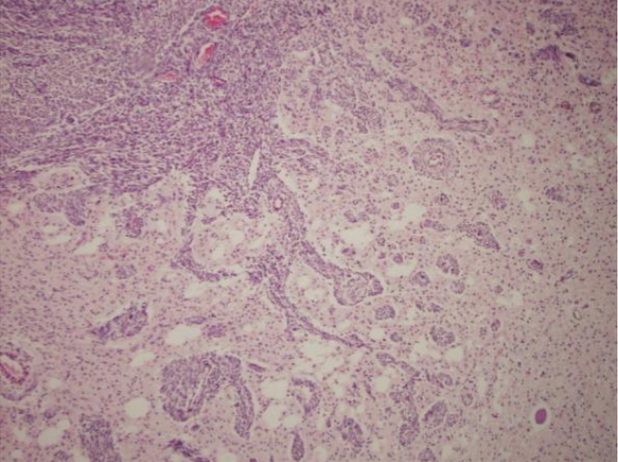

Examine the histological slide of this neoplastic lesion.

Which feature is most indicative that the tumor has metastatic potential?

Tumor cells invading adjacent tissue